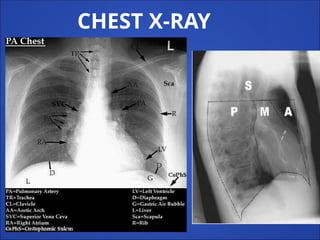

Radiological antomy

CHEST X-RAY